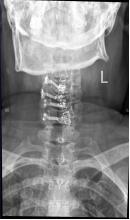

王阿姨今年66岁,半年前开始出现颈肩部疼痛伴双手麻木,并出现双足间断性麻木。为缓解疼痛,半年来,王阿姨自行口服药物治疗,多次就诊于市内三级医院,给予针灸、推拿等治疗,但期间症状反复发生,效果甚微,于是来到二一五医院骨科医院脊柱外科就诊。 脊柱外科许立新主任医师及其团队认真查体结合患者影像学检查,诊断王阿姨为:脊髓型颈椎病。由于王阿姨经半年保守治疗无效,颈髓压迫阶段长,综合考虑,许立新主任建议患者行颈椎后路手术治疗。

目前,脊髓型颈椎病后路手术方式多种多样,许立新主任医师团队通过反复阅片及查体,确定患者减压阶段,于是制定出后路颈椎单开门钉板内固定术,该手术方式既避免单开门手术因门轴断裂、再关门而导致手术失败,又避免了全椎板减压内固定术而导致术后患者颈椎活动丧失的并发症。向患者及家属告知后,遂行手术治疗,手术持续1.5小时,出血约100ml,手术顺利完成,术后,患者双手麻木及颈肩部疼痛症状明显缓解。